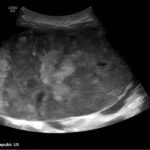

A 5-month-old female presented to the emergency department with worsening abdominal distention and postprandial emesis. Point-of-care ultrasound (POCUS) demonstrated extensive abdominal free fluid with a large, heterogeneous mass in the suprapubic region. This was confirmed on computed tomography (CT) of the abdomen and pelvis. The patient was urgently taken to the operating room for exploratory laparotomy where a ruptured tumor was discovered. The patient was eventually diagnosed with ovarian juvenile granulosa cell tumor. POCUS can be vital in guiding the recognition of rare pediatric conditions in the emergency department and should be considered in patients where there is concern for an acute abdomen.